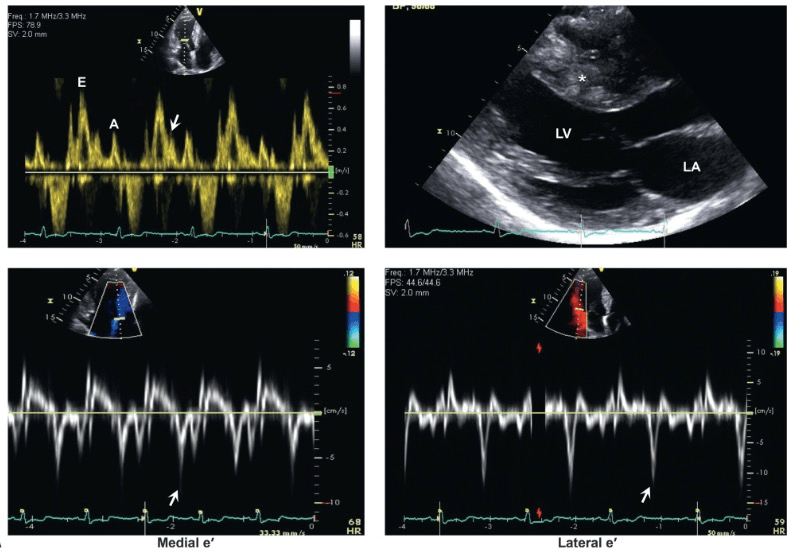

The diastolic function in this patient with normal LVEF

What is Normal Diastolic Function